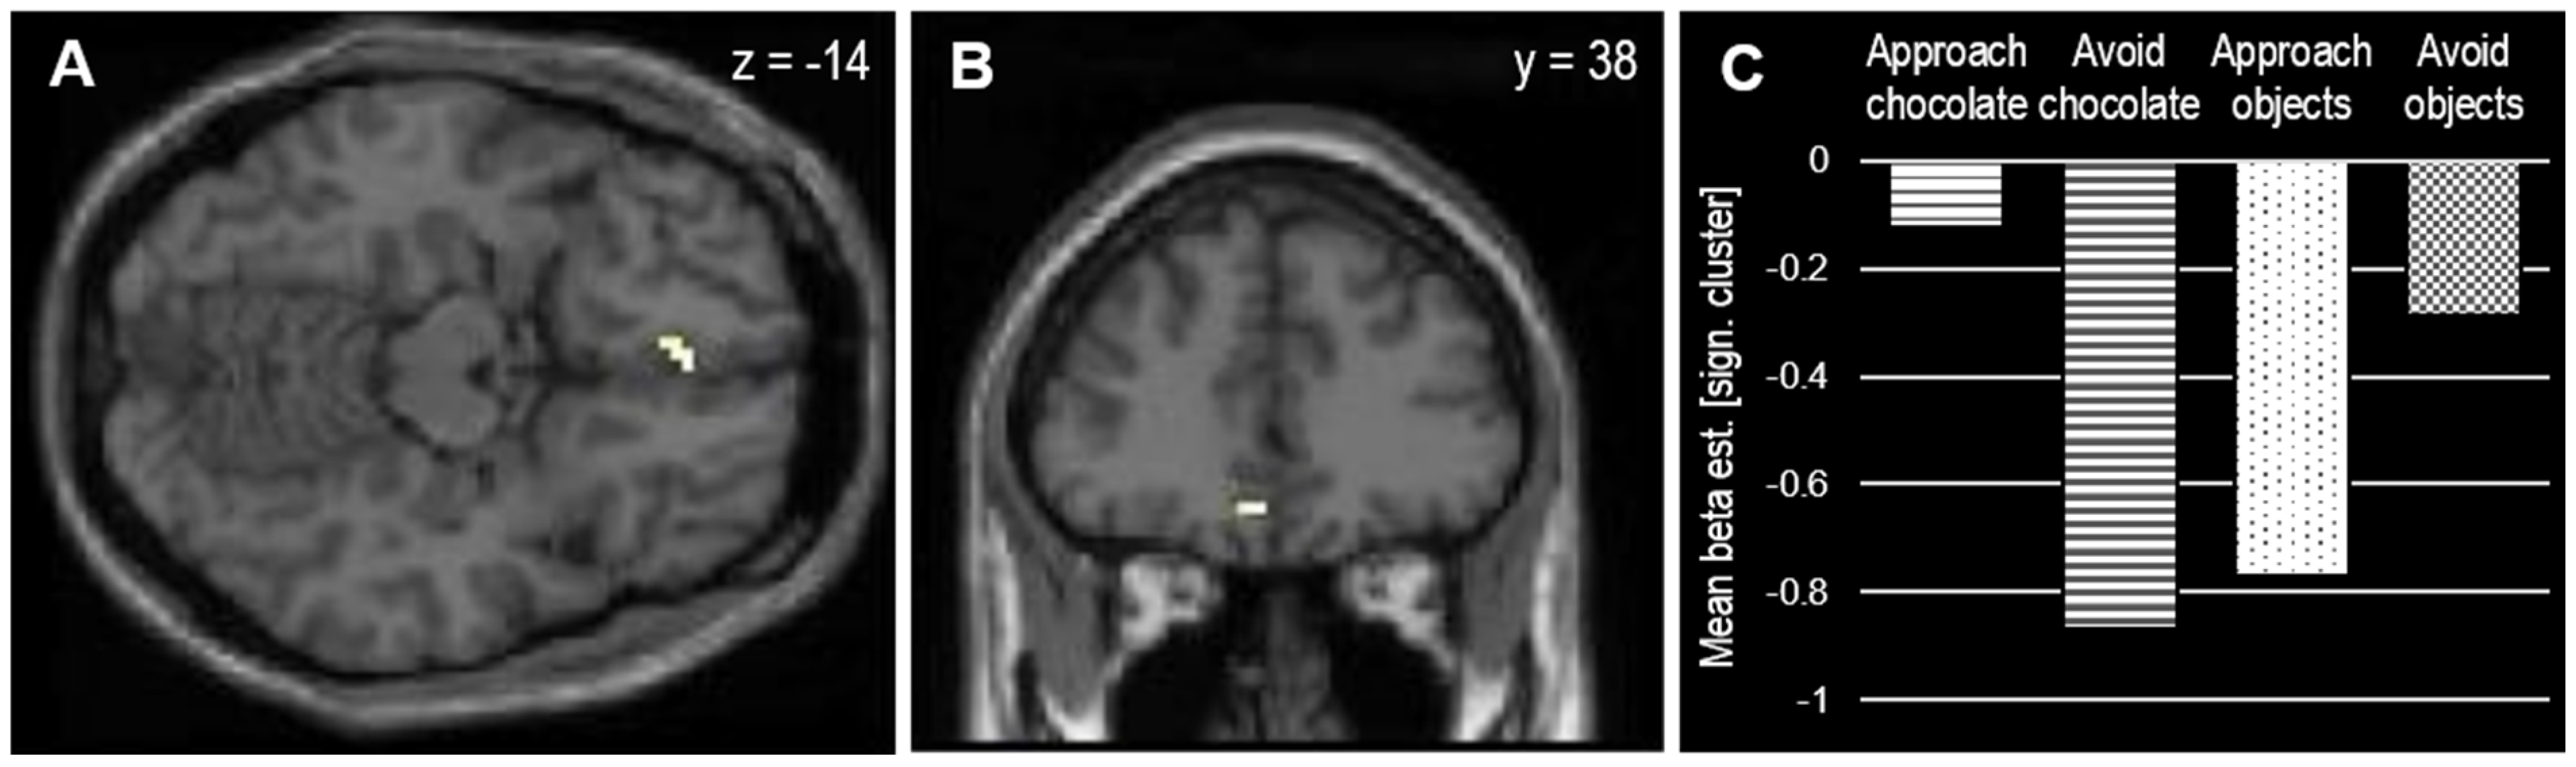

| Contrast | Brain Area | Voxels | MNI [x, y, z] | Tmax |

|---|---|---|---|---|

| Compatible > incompatible | ||||

| R medial occipitotemporal | 6 | 24, −76, −2 | 3.53 | |

| L medial orbitofrontal | 7 | −6, 38, −14 | 3.42 | |

| Incompatible > compatible | ||||

| L caudate nucleus | 7 | −6, −17, 7 | 4.05 |